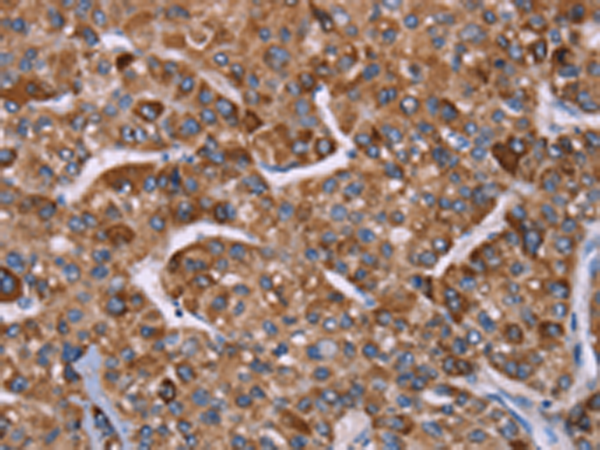

分类: 科研抗体货号: P11837别名: GIG8; ID2A; ID2H; bHLHb26应用: IHC反应种属: Human, Mouse, Rat